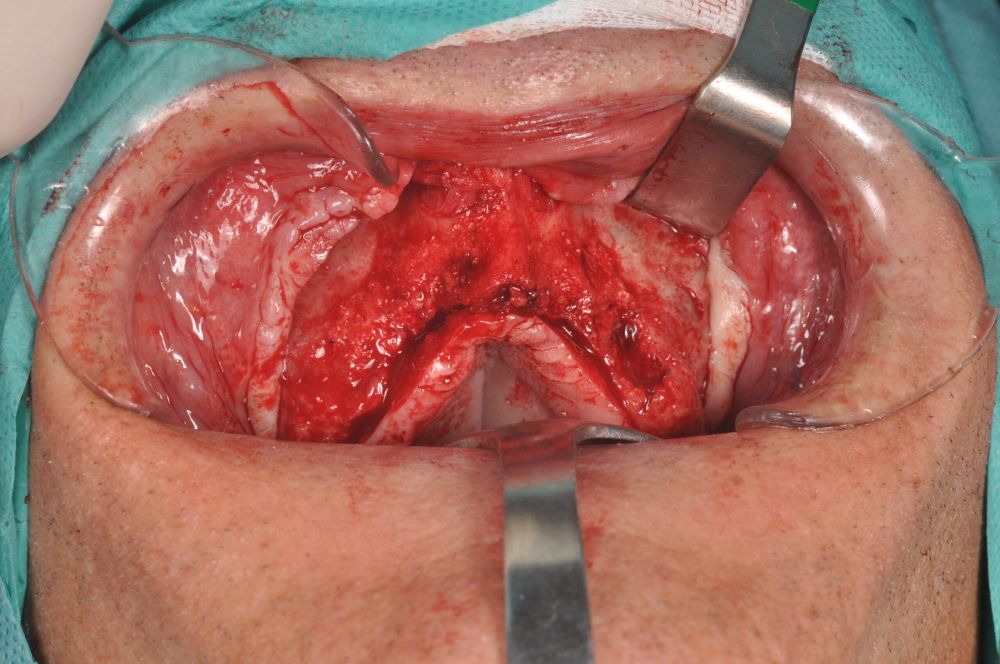

Clinical Case: A subperiosteal sintered titanium structure was fabricated with six transepithelial connections that were rehabilitated with an immediate implant supported fixed prosthesis made of PMMA. Two months later, a sintered chromium-cobalt framework with machined bases covered with acrylic resin teeth was fabricated as the final restoration. At one year follow-up, the case remains stable.